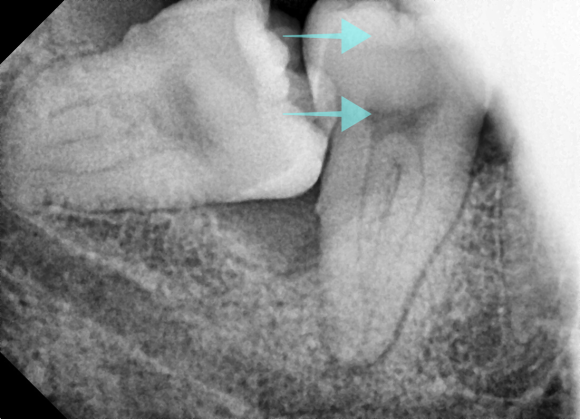

촬영일 : 240610

이번 환자분도 그런 케이스였습니다.

오른쪽 아래 사랑니(#48)가 잇몸 속에 절반쯤 묻혀 있었고

뿌리 방향이 신경관과 거의 닿아 있었는데요.

이 상태를 오래 두면 앞 치아를 밀면서

치근 흡수가 일어날 수 있기 때문에 즉시 발치가 필요했습니다.